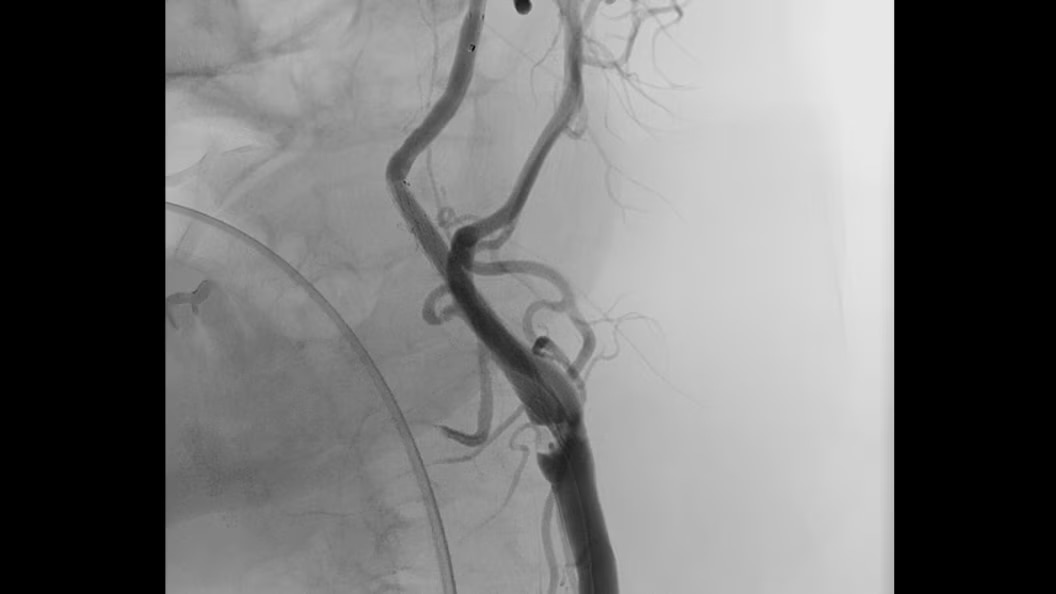

Embo ASSIST AI

Embo ASSIST1 with Virtual Injection, is a 3D Visualization software solution designed to help clinicians simulate injections dynamically and thus perform embolization procedures with confidence.